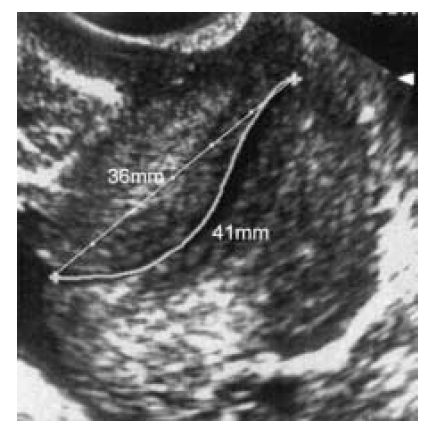

- The sonolucent endocervical mucosa should be identified as a guide to the true position of the internal os. The callipers should be placed to measure the linear distance between the triangular area of echodensity at the external os and the V-shaped notch at the internal os.